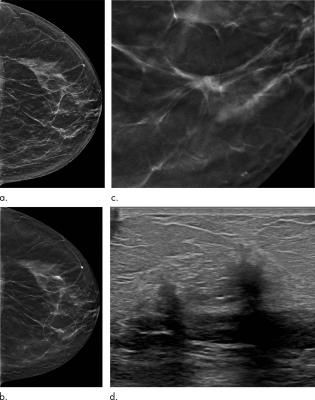

Masses In Mammography What Are The Underlying Anatomopathological